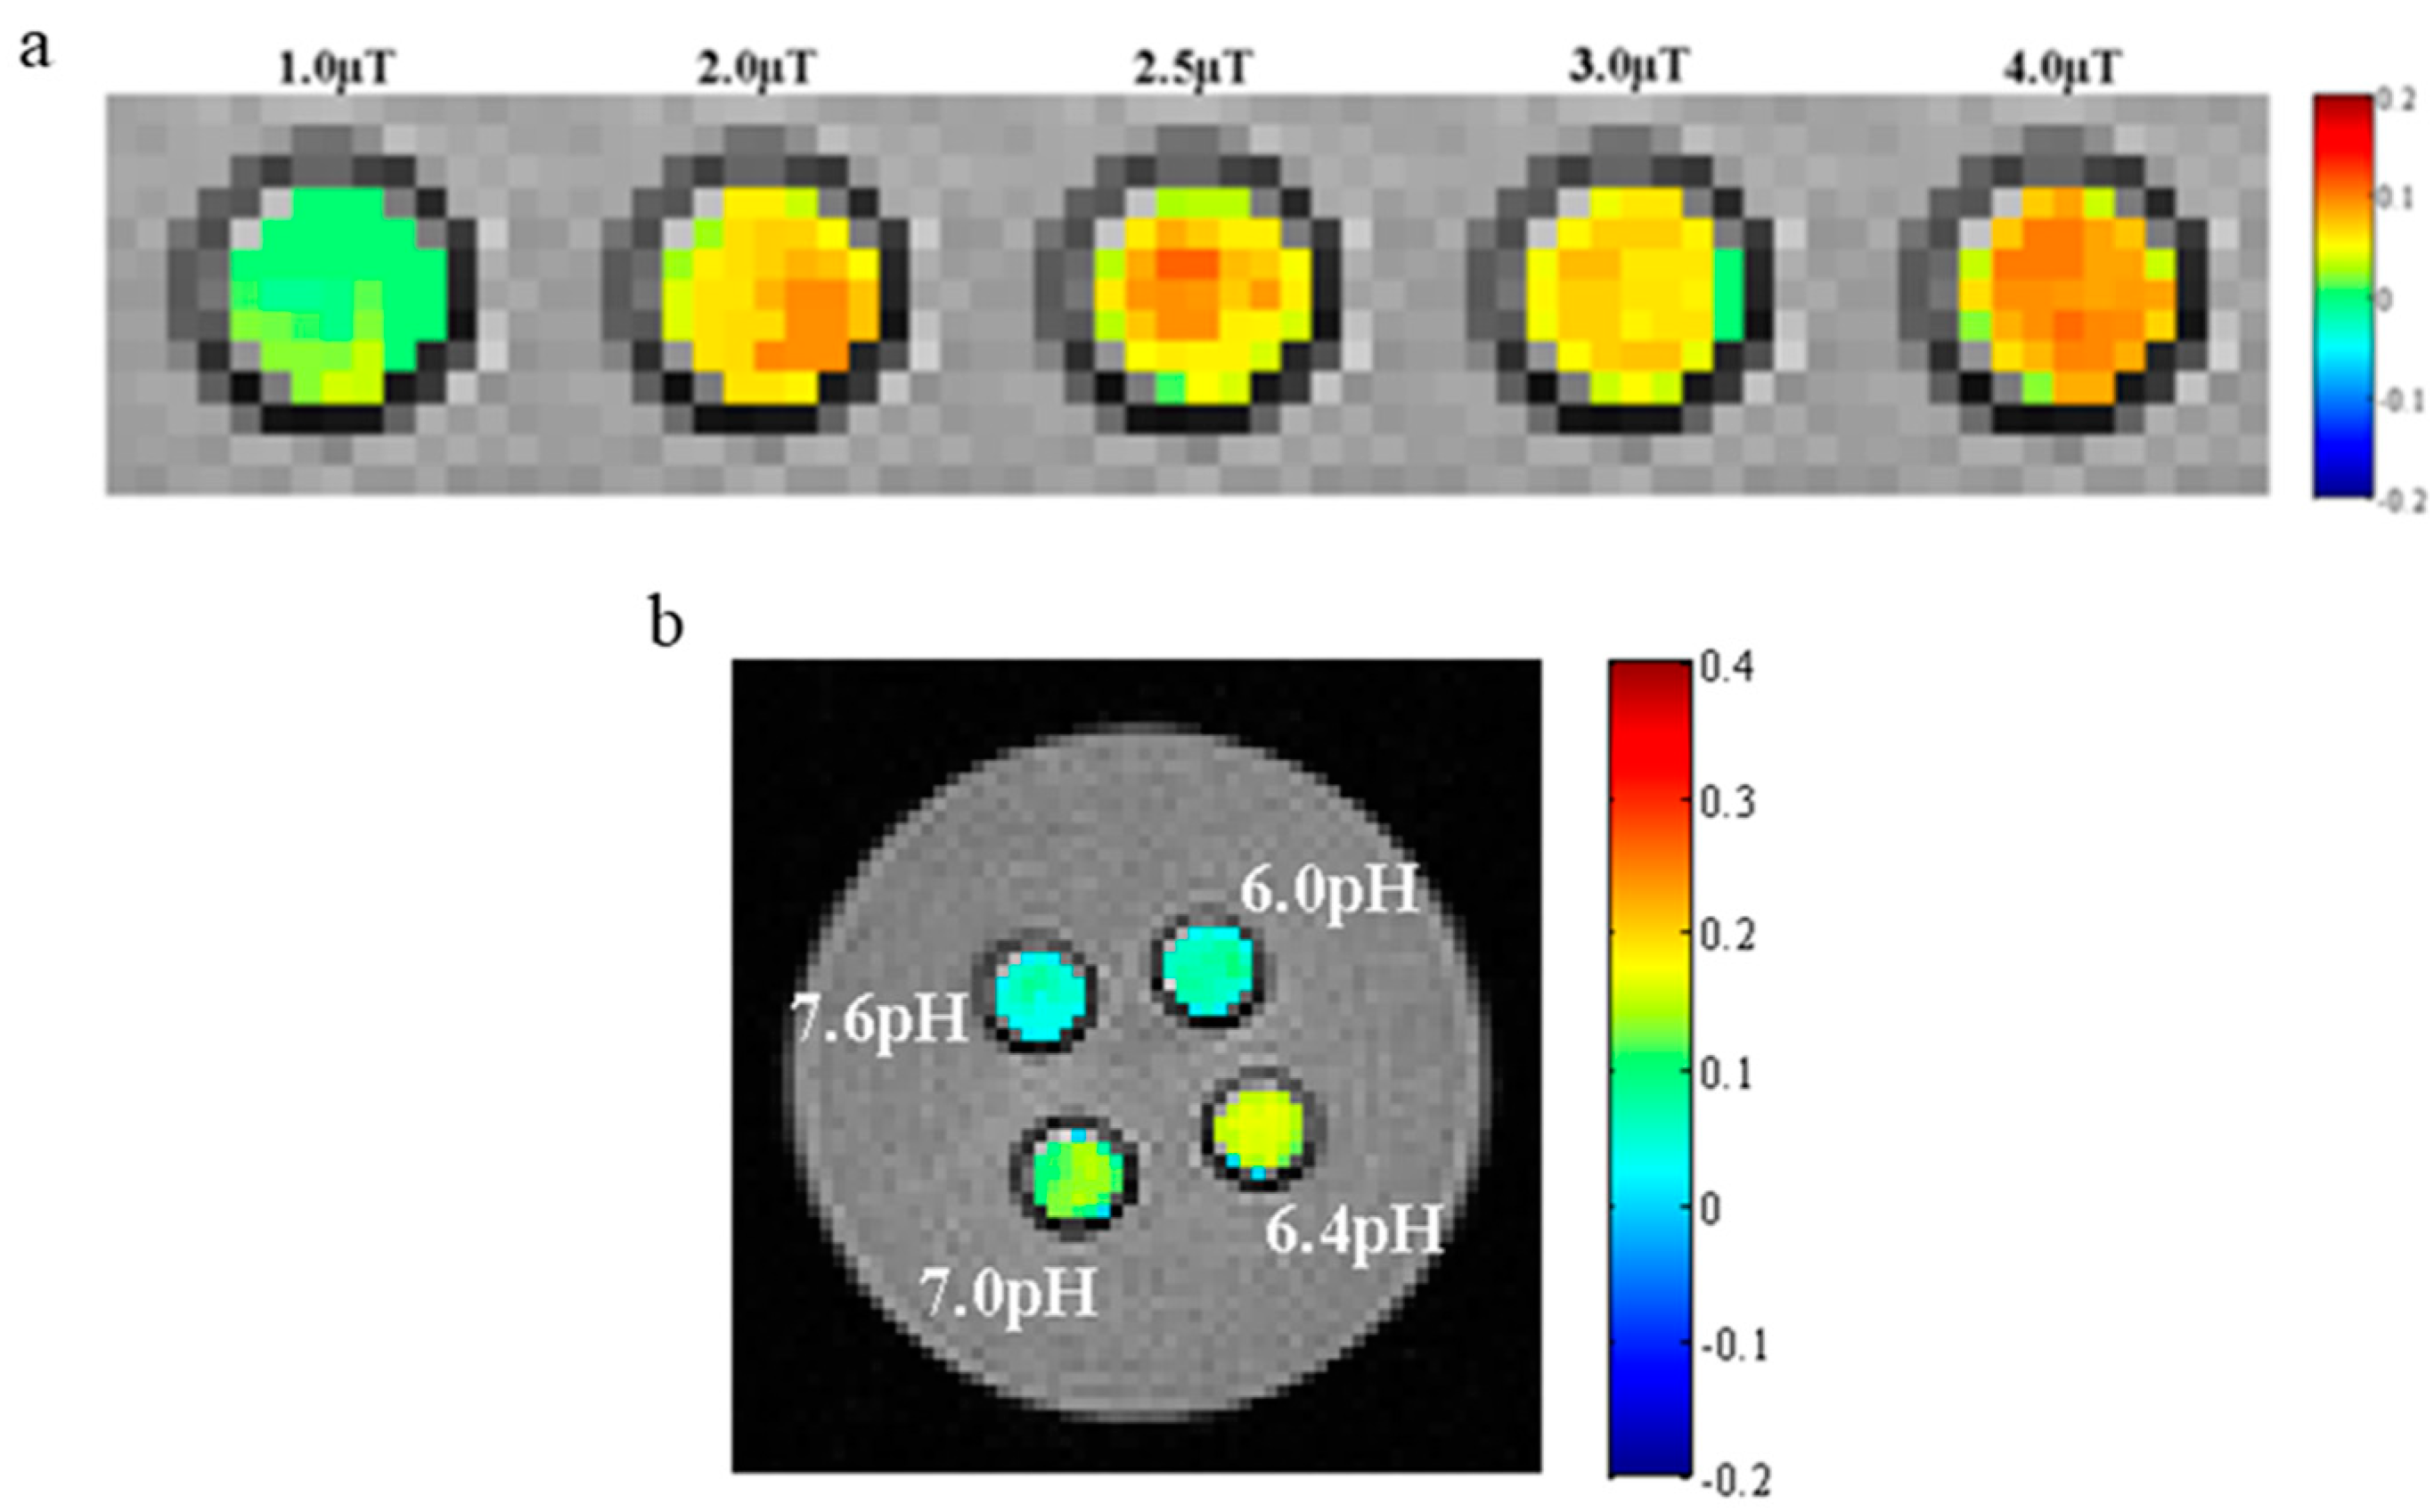

3.9. CEST MR Imaging In Vitro

3.10. CEST MR Imaging In Vivo